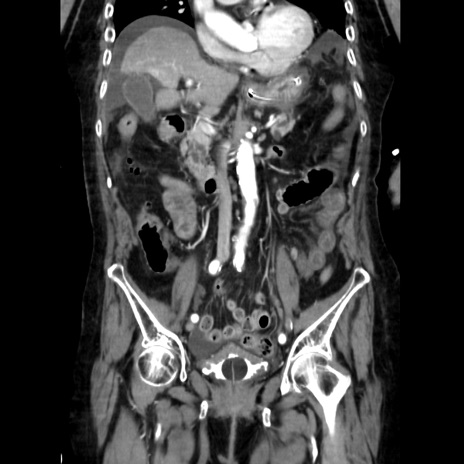

症例40(冠状断像)

【症例】90歳代女性

【主訴】腹痛・嘔吐

【現病歴】 食欲低下、嘔吐があり昨日他院受診。肺炎と診断され入院となる。入院後より腹部全体に圧痛あり。胃管留置され経過みていたが、症状持続するため、

当院転院となる。

【既往歴】胸椎圧迫骨折、胆石症

【身体所見】腹部:中央に激痛あり、圧痛あり、反跳痛不明

【データ】WBC 17100、CRP 18.82

冠状断像